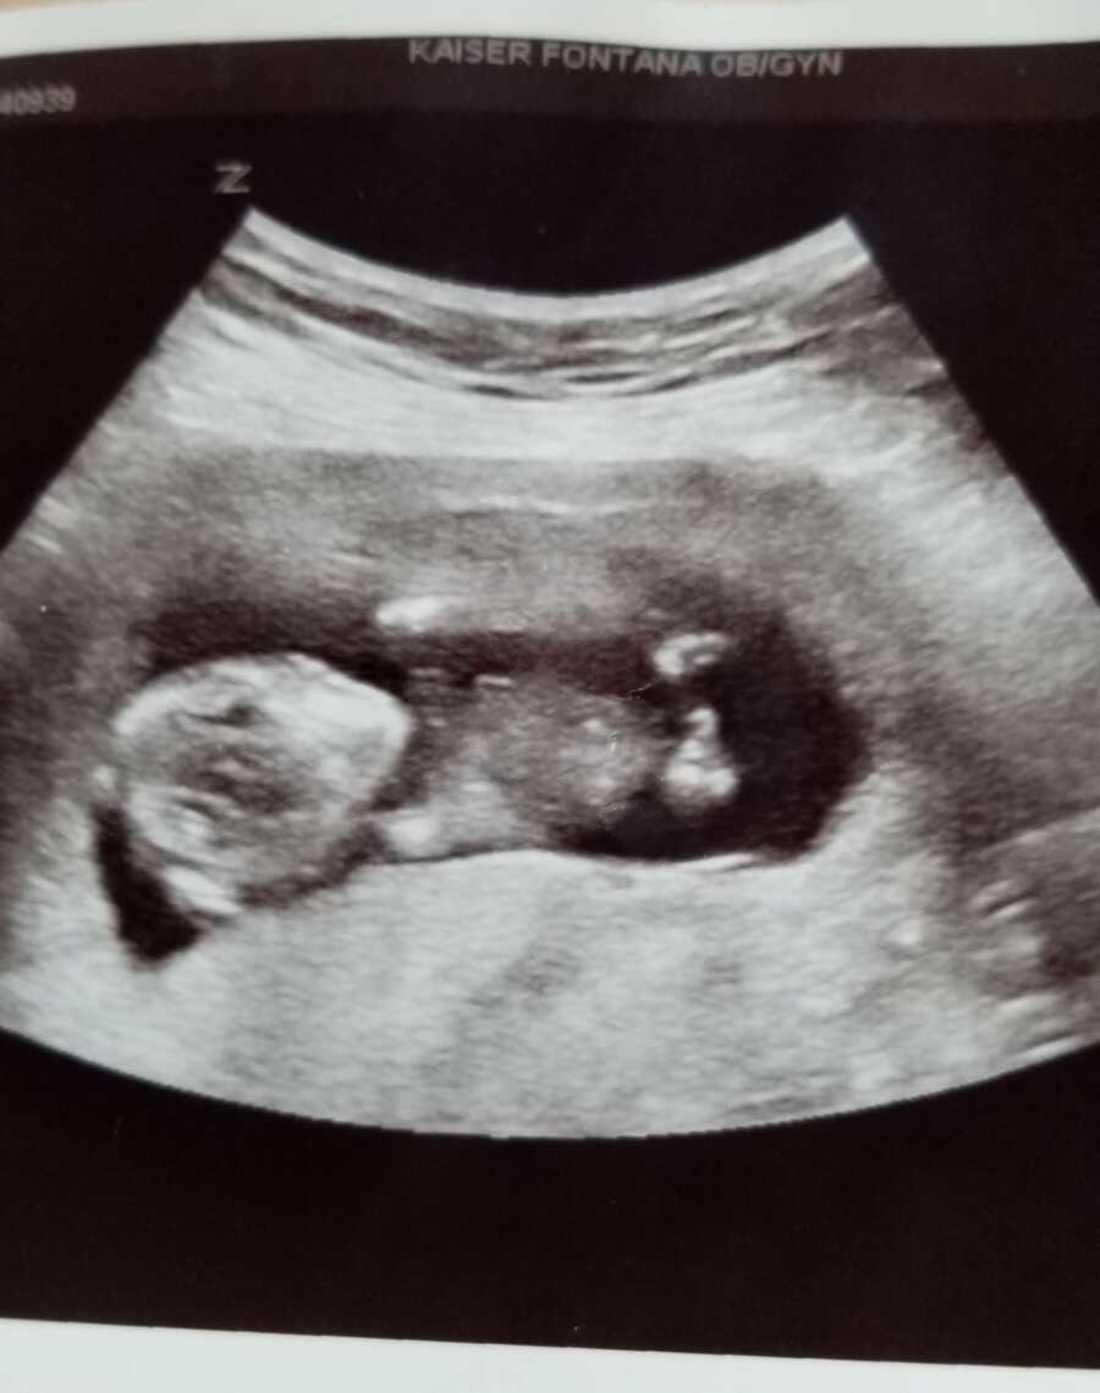

However, when I was 30 weeks along, I had a dream I gave birth to a baby boy with a head full of hair, but he was very sick in the NICU. This gave me a lot of anxiety, and I thought maybe it meant we would have a difficult birth and end up having to transport. I packed bags, in case we needed to transport, and installed the car seat.

My entire pregnancy was uneventful. I was healthy. The baby was healthy.